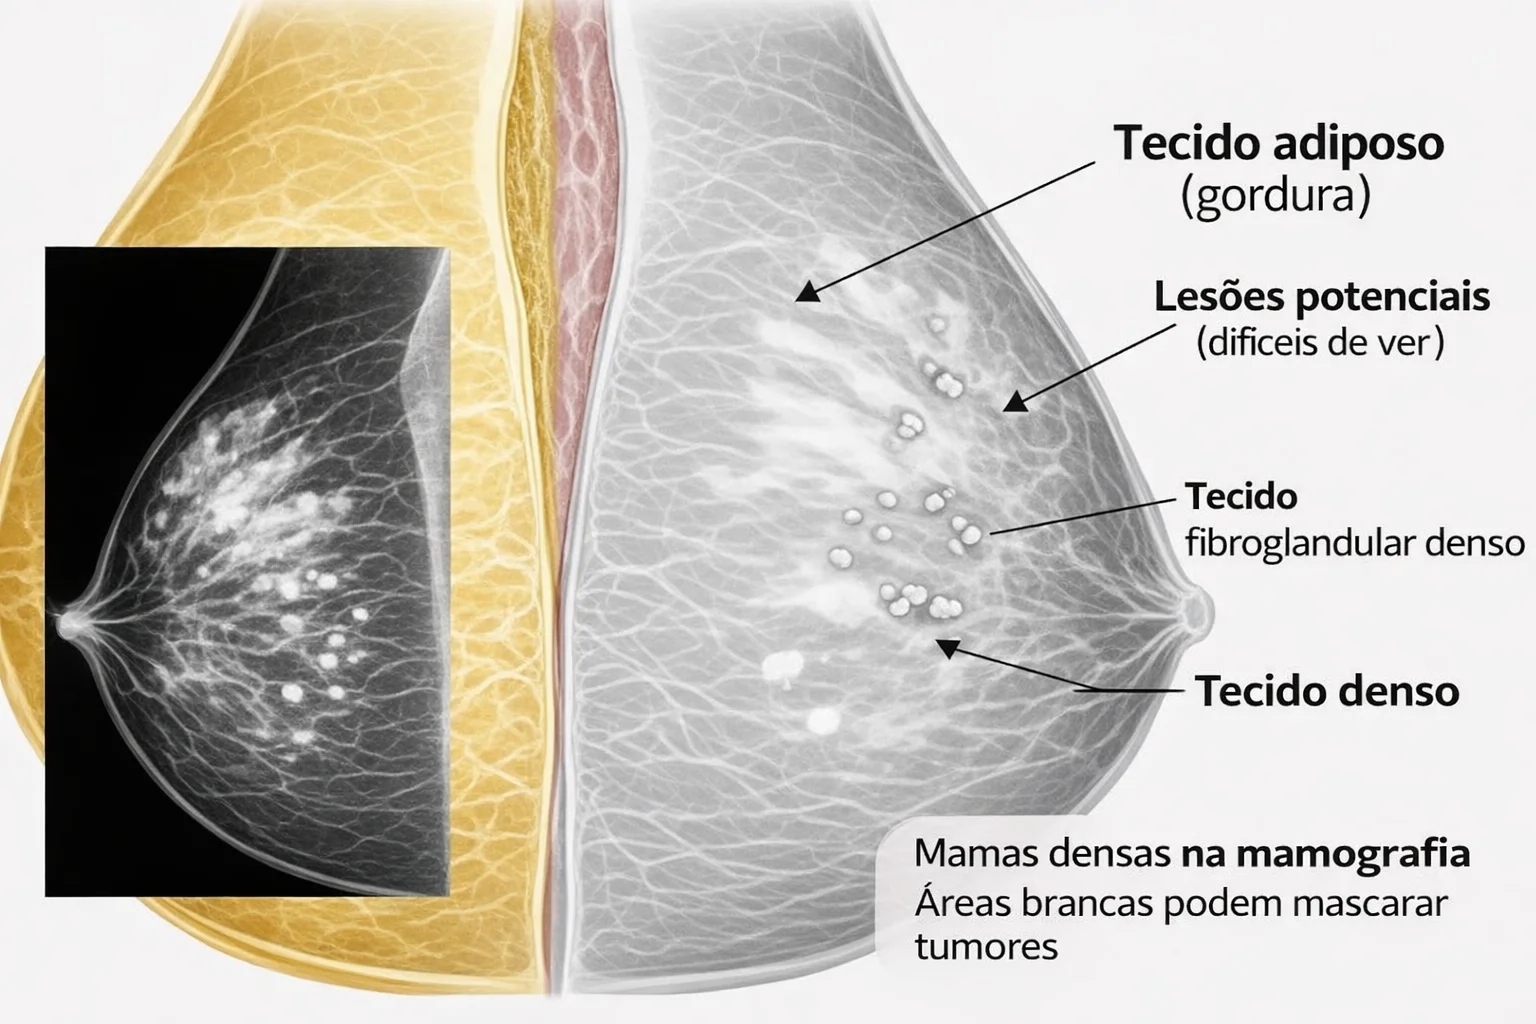

Mamas Densas: o que significa no exame e como impacta no rastreamento Quando você faz uma mamografia, o laudo pode...